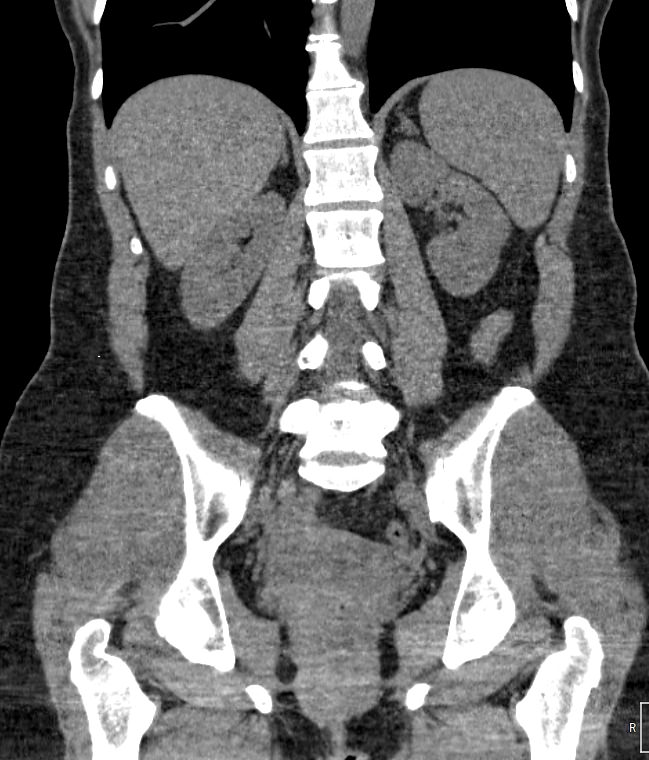

Методика КТ позволяет оценить анатомическое строение почек, надпочечников, состояние мочеточников и мочевого пузыря, кроме того, дает возможность визуализировать сосудистую систему и регионарные лимфатические узлы.

Сканирование применяется для выявления воспалительных заболеваний почек, чашечно-лоханочной системы, мочеточников и мочевого пузыря, также позволяет обнаружить конкременты на фоне мочекаменной болезни, диагностировать доброкачественные и злокачественные новообразования, точно классифицировать кистозные образования по системе Bosniak, что особенно важно для урологов и нефрологов, а также определить степень поражения регионарных лимфатических узлов. Кроме того, КТ используется для диагностики травматических повреждений органов мочевыделения, аномалий развития почечно-лоханочной системы, дает максимальную информацию для хирурга при планировании оперативного вмешательства.

Что показывает КТ почек, мочеточников, мочевого пузыря

- опущение почек;

- аномалии развития почек, мочетоников

- доброкачественные и злокачественные новообразования;

- камни (конкременты);

- уретероцеле

- сосудистую патологию (сосудисто-мочеточниковый конфликт, инфаркт почки);

- последствия оперативных вмешательств;

- увеличение лимфоузлов в брюшной полости, забрюшинном пространстве и малом тазу;

- травматические изменения

- патологии сосудов малого таза.